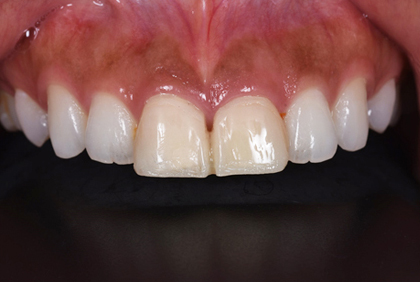

途中経過

患者様の主訴は、「保険の黄色くなったかぶせ物を白くしたい」でした。

保険のかぶせ物は、プラスティックで白い部分を作成するので、どうしても経年劣化で黄色く変色してきます。また、この患者さんは、横から見るとその歯がだいぶ前に出ていたために、少し出っ歯にも見えていました。

保険のかぶせ物を除去して、仮歯に置き換えて、その後プロビジョナルと言われる最終的な仮歯をセットして歯肉の状態を確認します。問題がないことを確認してから、最終的な型採り試適の後に最終的なセラミックのかぶせ物をセットしました。